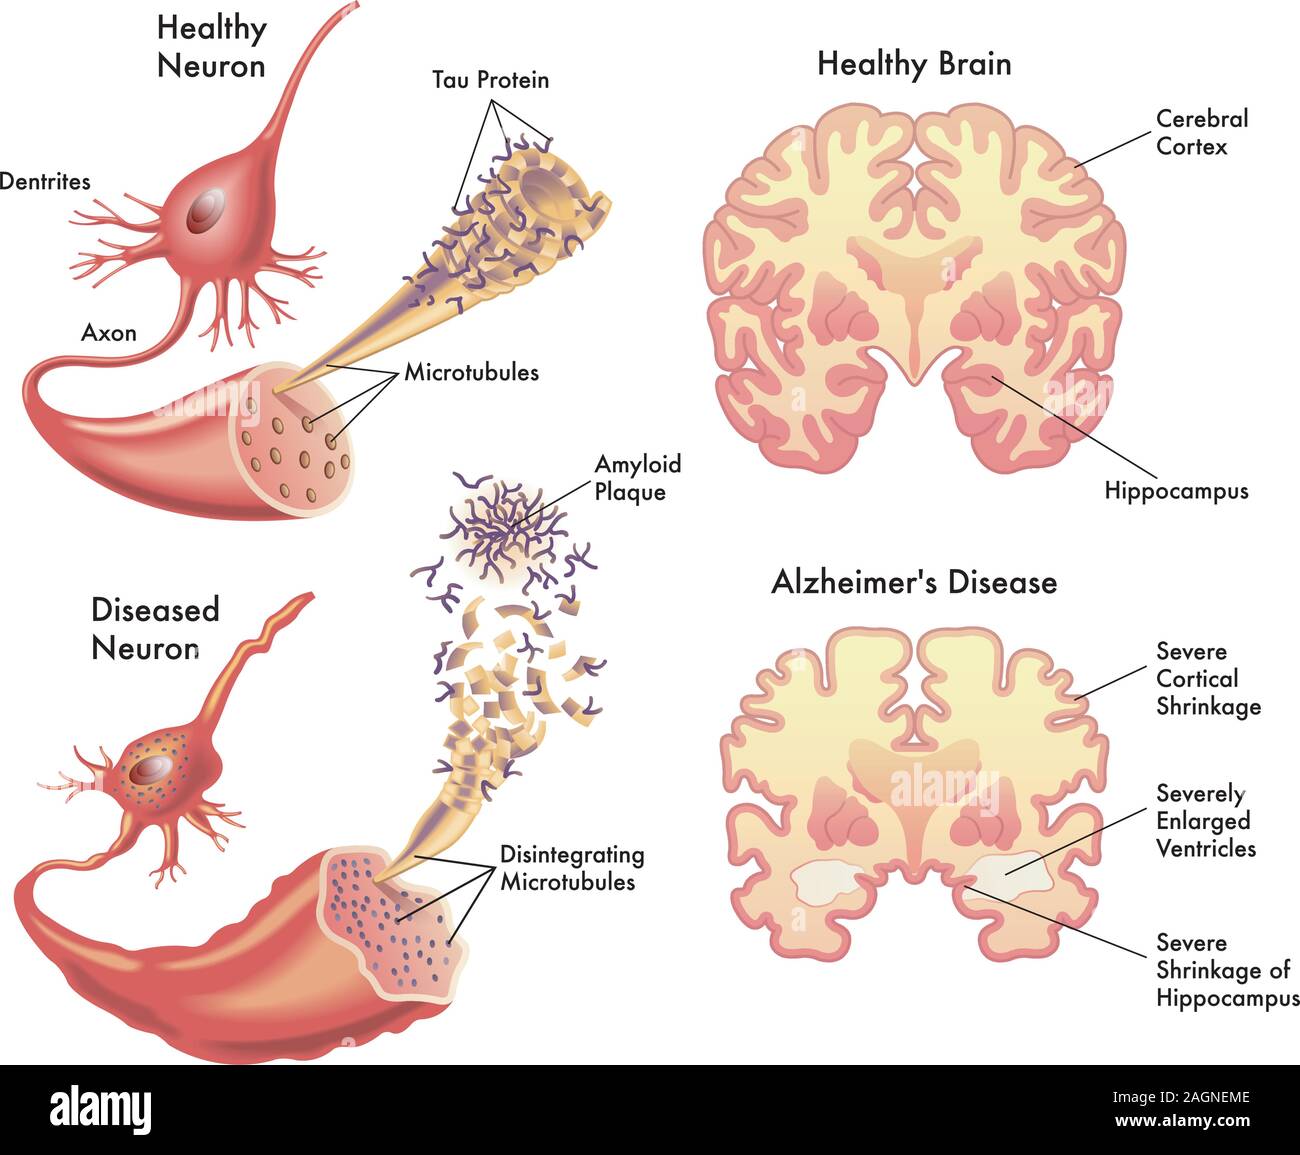

RF2XARW8C–Morbo di Alzheimer. Neurodegenerazione. Sezione trasversale del cervello normale e Alzheimer, con atrofia della corteccia cerebrale, ventricoli ingrossati e Hipp

RF3BH7B1F–Morbo di Alzheimer. Neurodegenerazione. Sezione trasversale del cervello di Alzheimer, con atrofia della corteccia cerebrale, ventricoli ingrossati e ippocampo. Un

RF2WNK1GK–La struttura di un neurone malato e sano. Neurone danneggiato. Malattia di Alzheimer. Malattia cerebrale demenza, disturbi della memoria. Un neurone nell'Alzheimer

RF2FM2W9M–L'Alzheimer, è una malattia neurodegenerativa. Demenza. Confronto e differenza tra cervello sano, morbo di Alzheimer grave e cognitivo lieve